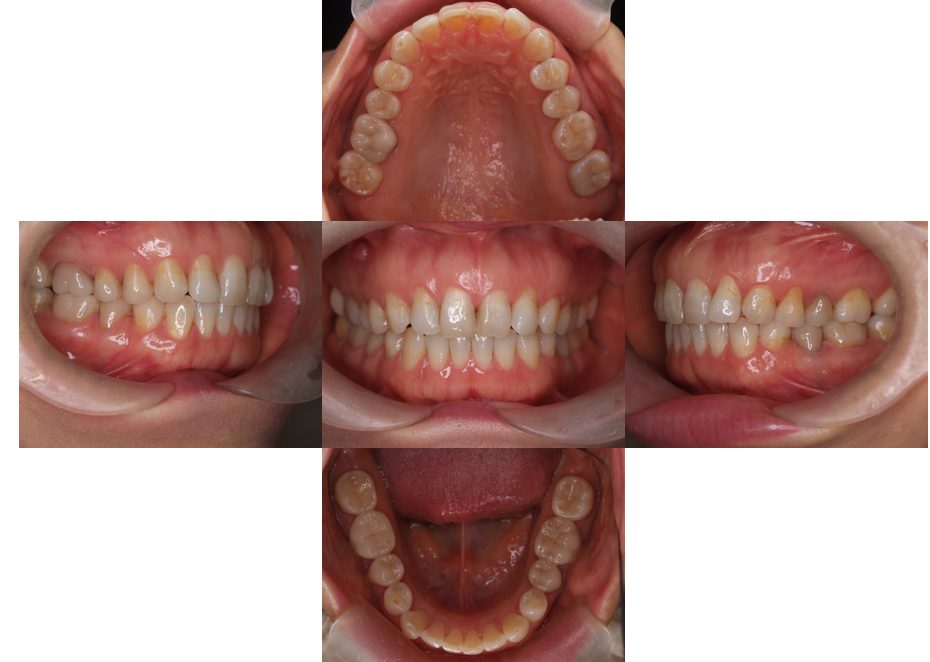

矯正治療・根管治療・補綴治療の症例紹介(三隅歯科クリニック)

三隅 賢祐(三隅歯科クリニック)

症例詳細

| 主訴 | 過去作成した右下の被せ物がずれて入っており、たまに腫れる。歯並びも気になる。 |

| 治療内容 | 矯正治療を行いました。 |

| 治療費 | 800,000円(税込み) |

| 治療期間 | 2年半(矯正治療期間 2年) |

| 治療回数 | 30回 |

| 想定されたリスク | 術前に基礎資料を整え分析し、セットアップモデル等でシミュレーションをしておかないと、予定通りの治療が行えないリスクがあった。 |